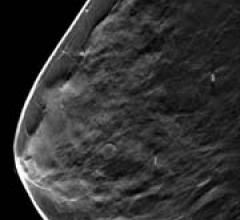

Despite decades of progress in breast imaging, one challenge continues to test even the most skilled radiologists ...

Until recently, consistent assessment of breast composition was hampered by widely differing technical factors and the ...